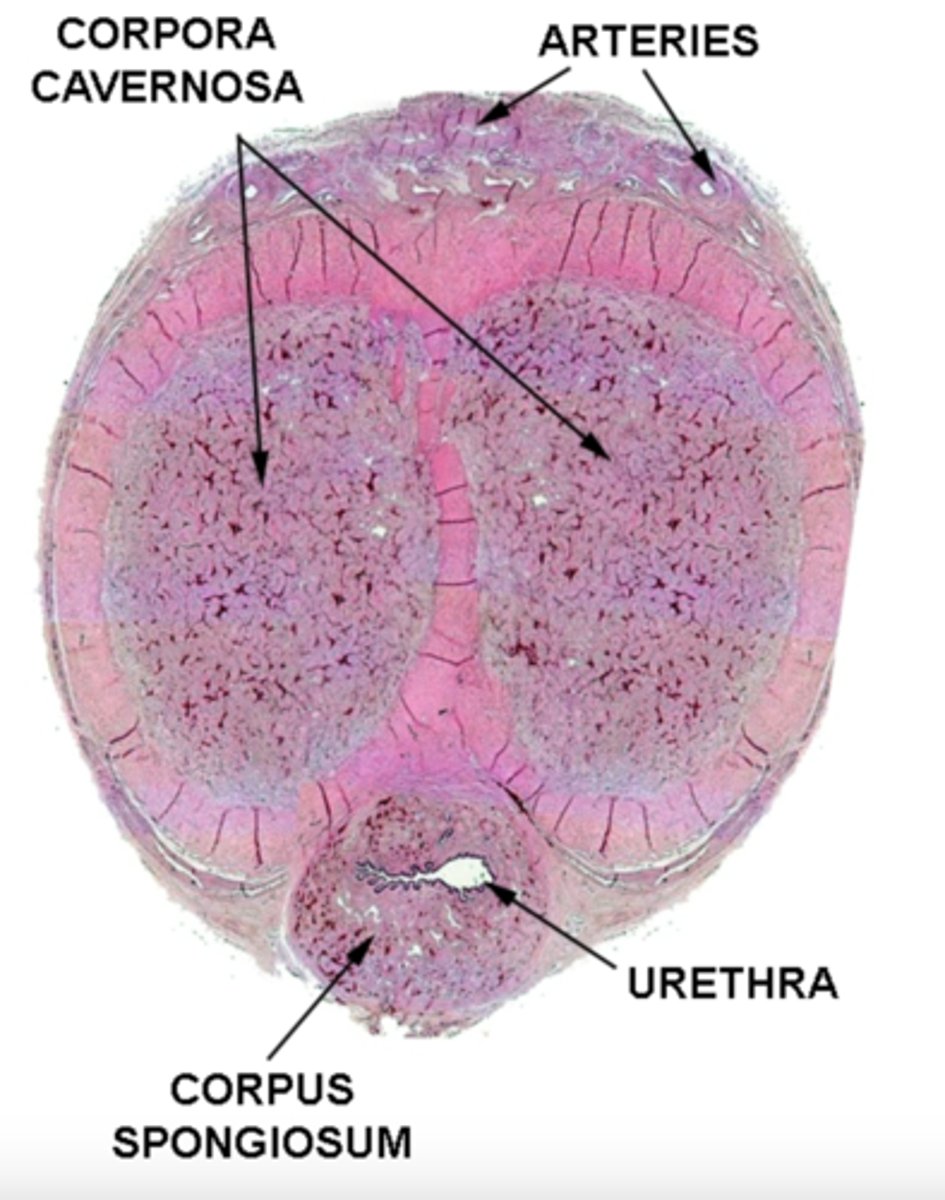

where are the corpus spongiosum and corpus cavernosum located?

spongiosum: surrounds urethra

cavernosum: above the corpus spongiosum

what is the function of the corpus spongiosum?

spongiosum 'buffers' urethral lumen from pressure of the cavernosa during erection (prevents urethral collapse)